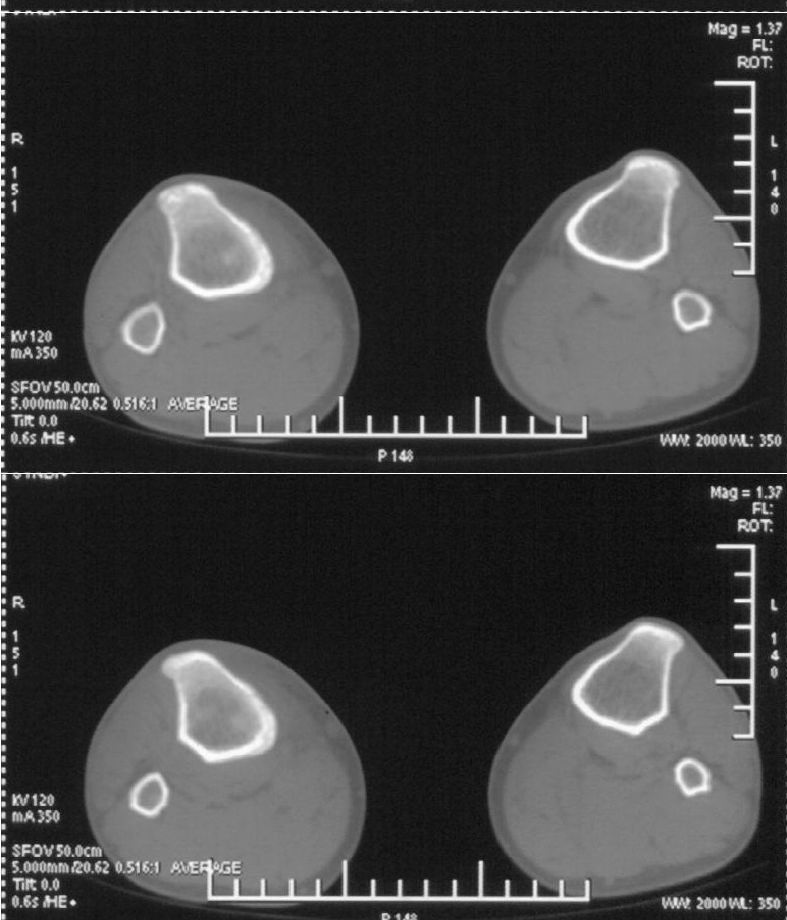

男,42岁。4个月前钢筋钝伤右侧小腿部,当时因无明显外伤,未引起重视。一周后因受伤腿部疼痛,发现肿胀,随后到当地医院进行检查(2008年4月16日)。因未发现骨质异常未引起重视,仅仅进行口服抗生素治疗处理。经过一段时间治疗但未见明显治疗效果在5月29日又进行x线检查,发现有胫骨密度上段密度增高,又进行抗炎治疗,仍未见效果。又在7月3日进行x线检查,仍然报告有胫骨上端密度增高,并建议ct检查。以下是相关检查结果:

该患者到某三级医院进行会诊,并重新作了平片检查,认为畸形性行骨炎:

髓腔密度呈絮状增高,胫骨上端内侧可见层状骨膜反应,考虑骨髓炎.

髓腔密度呈絮状增高,胫骨上端内侧可见层状骨膜反应,肌间隙模糊,考虑骨髓炎.

破坏、增生、骨膜反应,考虑骨髓炎